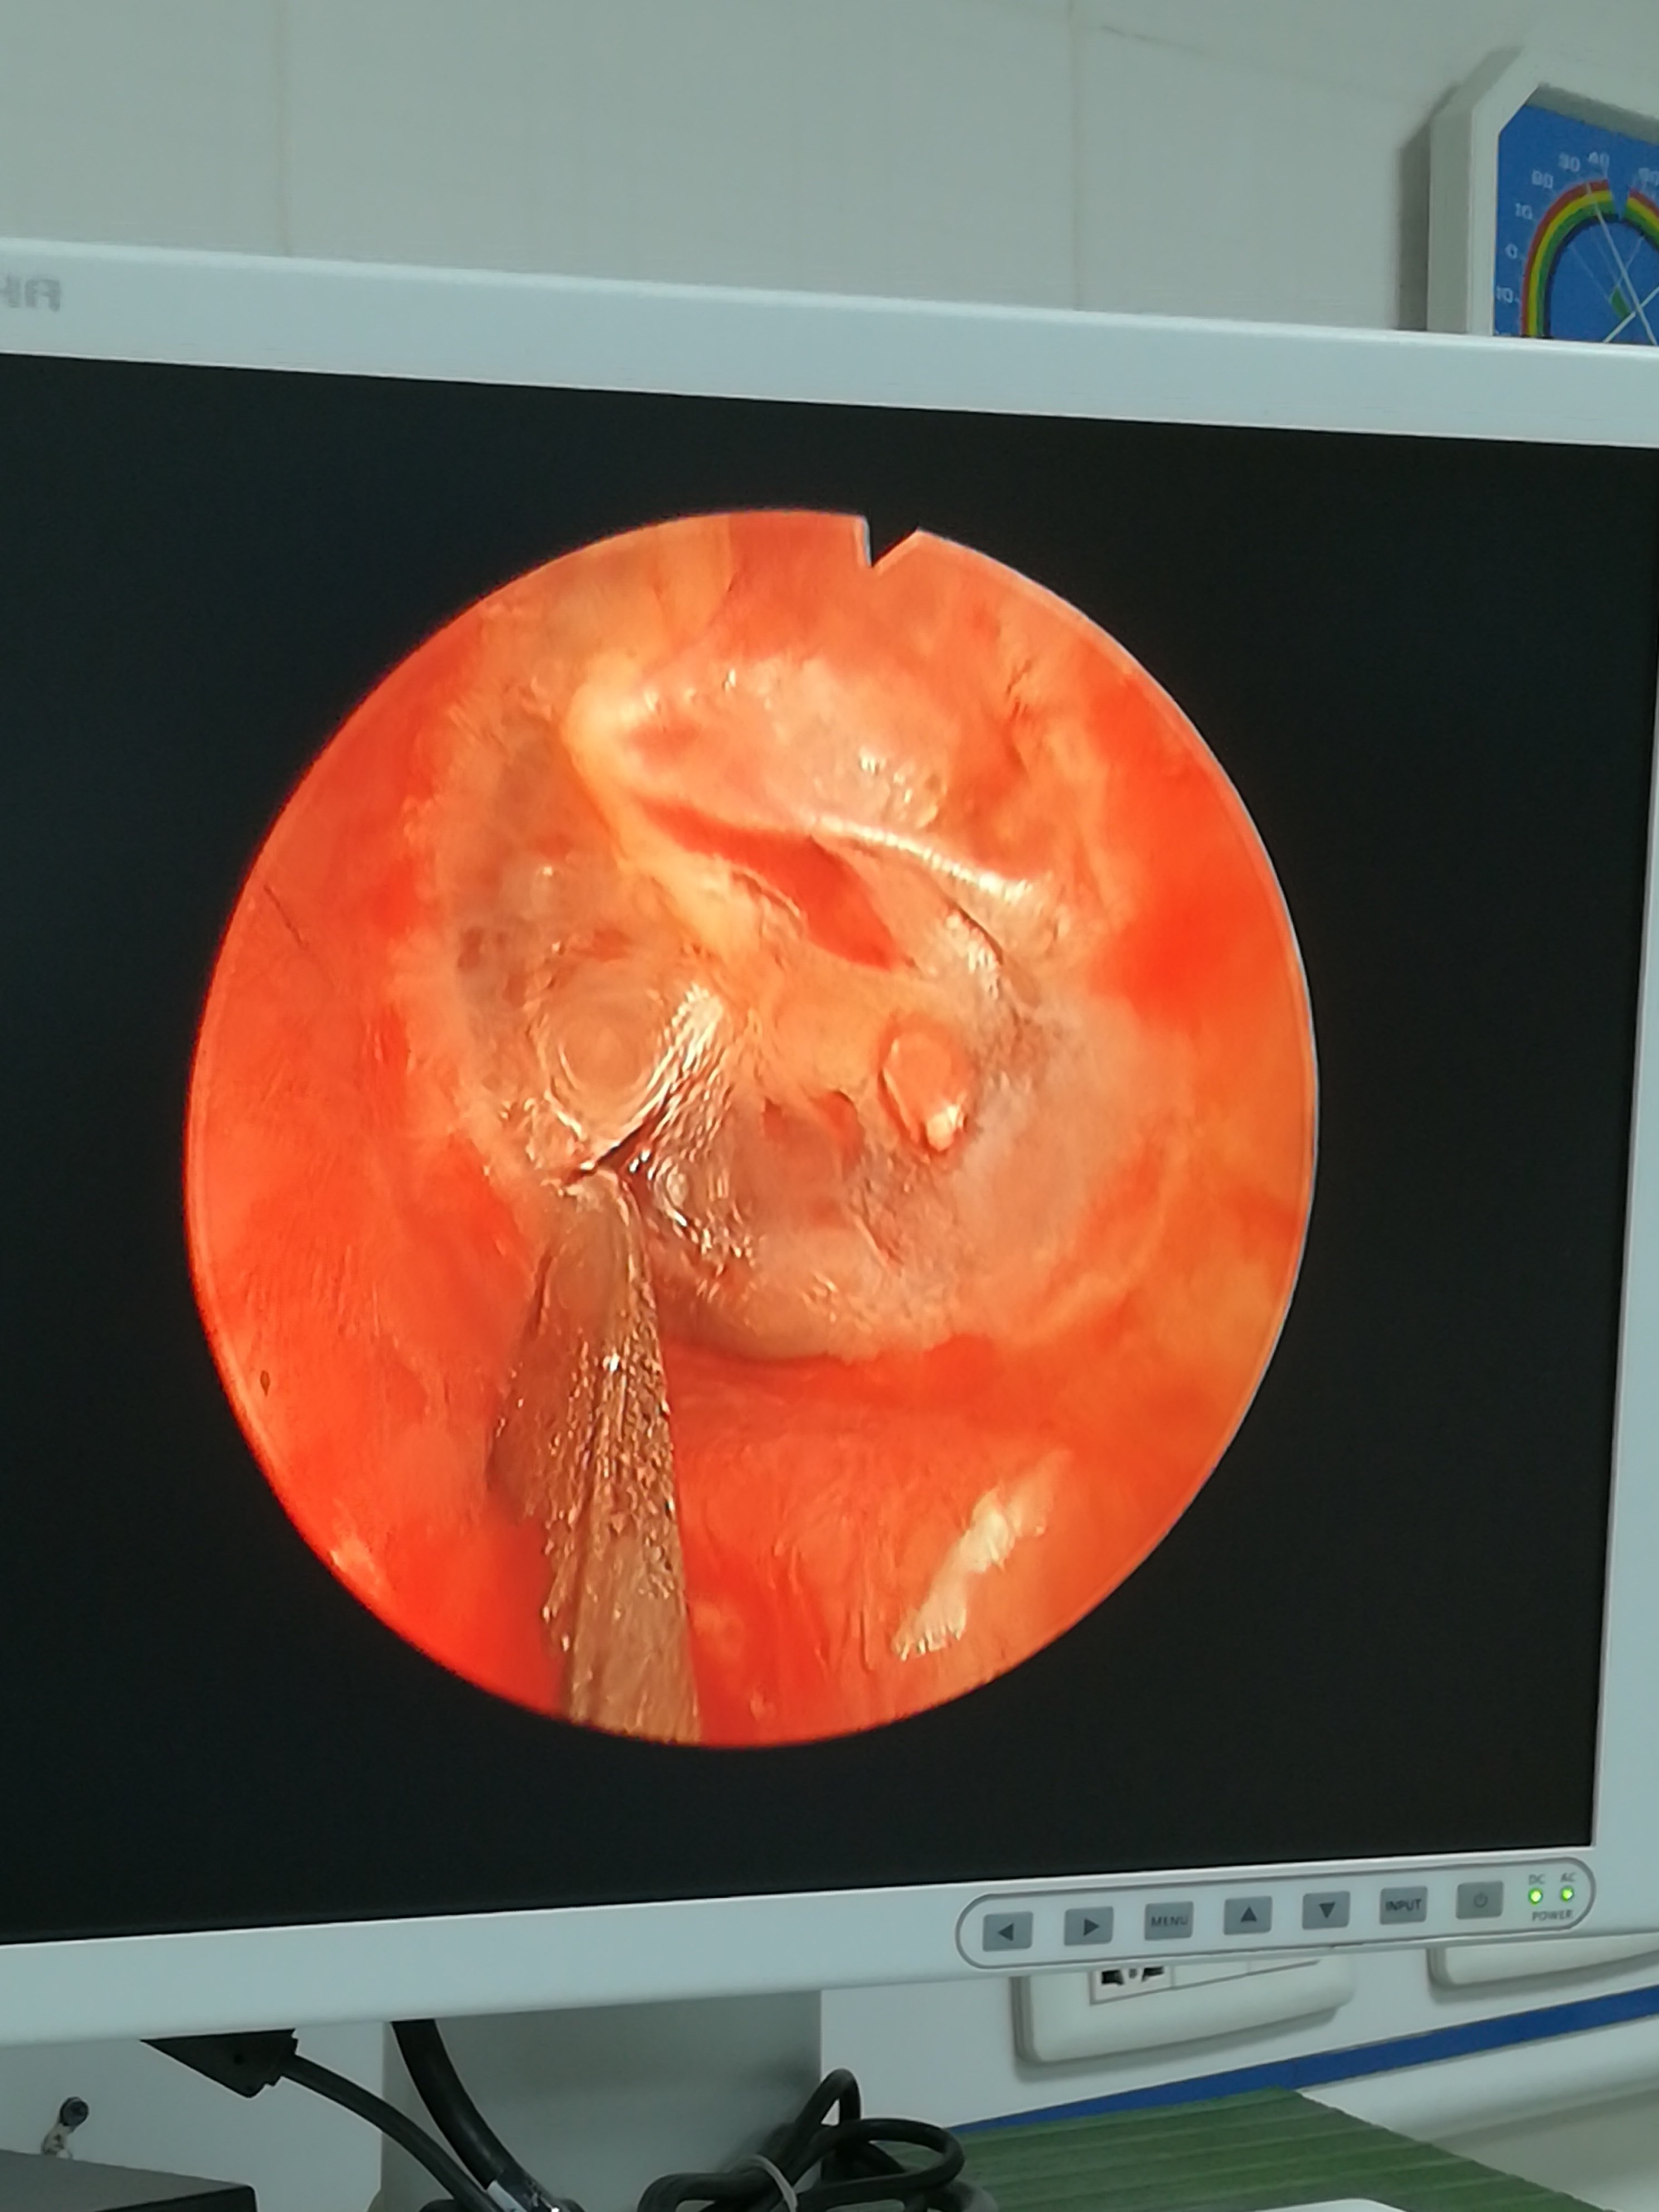

3、分泌性中耳炎的治疗治疗原则为针对病因清除积液恢复听力,具体方案需根据病因和病情严重程度制定1病因治疗 咽鼓管功能障碍若由腺样体肥大鼻息肉等阻塞咽鼓管开口导致,需通过手术切除腺样体或切除鼻息肉,恢复咽鼓管通气上呼吸道感染若因鼻窦炎咽炎等感染引发,需使用抗生素如阿莫西林;1 抗生素当分泌性中耳炎由细菌感染引发时,抗生素是消除感染的核心药物外用滴耳剂如盐酸左氧氟沙星滴耳液,可直接作用于中耳,抑制敏感菌生长口服抗生素如头孢呋辛酯片,适用于全身性细菌感染或外用效果不佳的情况需注意,抗生素仅对细菌感染有效,滥用可能导致耐药性,因此需严格遵医嘱使用2;中耳炎的最佳治疗方法需根据类型确定,主要分为以下两类分泌性中耳炎鼻喷剂治疗使用减充血剂和鼻腔应用类固醇激素,以及生理海水生理盐水冲洗鼻腔,以缓解鼻腔炎症和肿胀,有助于改善咽鼓管功能促排剂治疗使用促进黏液分泌物排出中耳腔的药物,帮助中耳积液排出,减轻症状化脓性中耳炎全身;手术治疗 鼓膜穿刺当保守治疗无效,中耳积液较多时,可通过鼓膜穿刺抽出积液,迅速缓解症状 鼓膜切开或鼓膜切开加置管术对于鼓膜穿刺效果不佳或反复积液的患者,可考虑进行鼓膜切开或鼓膜切开加置管术,以长期保持中耳通气和引流注意事项 治疗分泌性中耳炎时,应首先明确病因,如鼻腔鼻窦鼻咽;分泌性中耳炎是由于反复上呼吸道感染而引起了急性鼻炎,造成咽鼓管发炎中耳腔内有积液,通过耳内镜检查可以从耳膜处看到液平面,听力检查出现传导性聋,患者出现耳闷听力下降耳鸣需要给予药物治疗,如抗生素黏液促排剂糖皮质激素鼻黏膜收缩剂,联合应用一周以上,一般可以控制急性症状,但是如果;儿童慎用耳毒性药物,严格遵医嘱控制剂量老年人症状可能不典型,出现耳闷听力波动时需及时排查孕妇优先选择局部用药如滴鼻液,避免口服药物对胎儿的影响分泌性中耳炎积液若未及时干预,可能发展为粘连性中耳炎或胆固醇肉芽肿,导致永久性听力损伤早期诊断与规范治疗是关键,建议出现耳部症状。